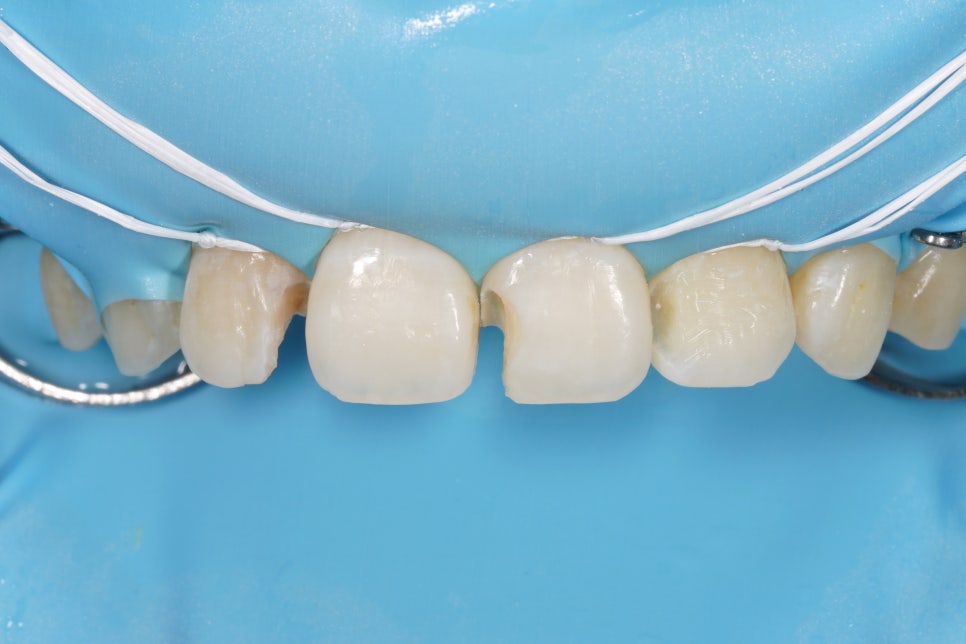

치료완료

그리고 치료가 마무리된 사진입니다.

어떤가요, 자연스러운가요?

치아가 동글동글 이쁘고 귀엽네요